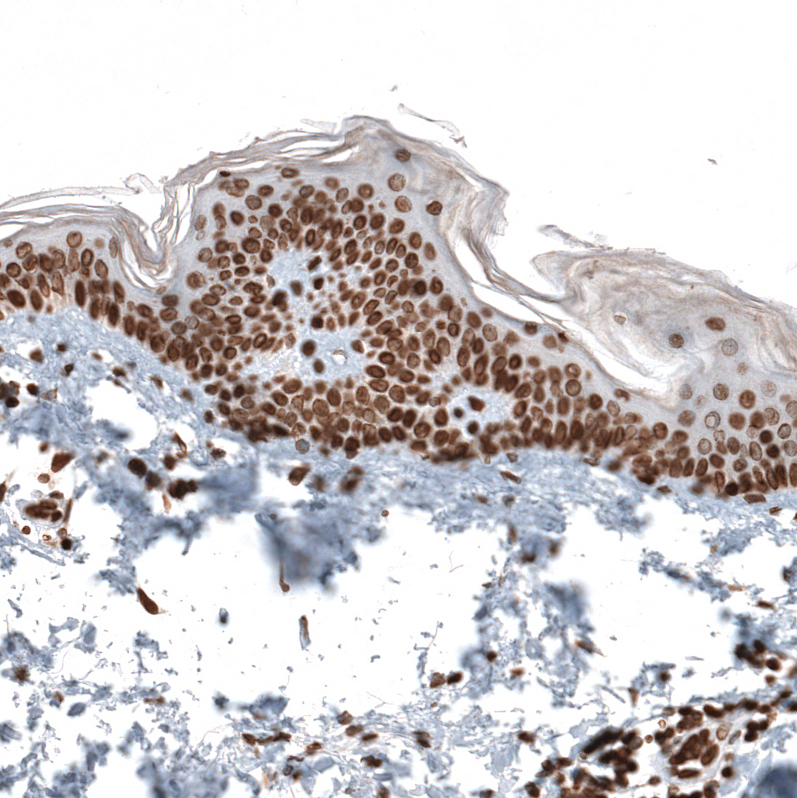

Immunohistochemical staining of human skin shows strong nuclear positivity in squamous epithelial cells.